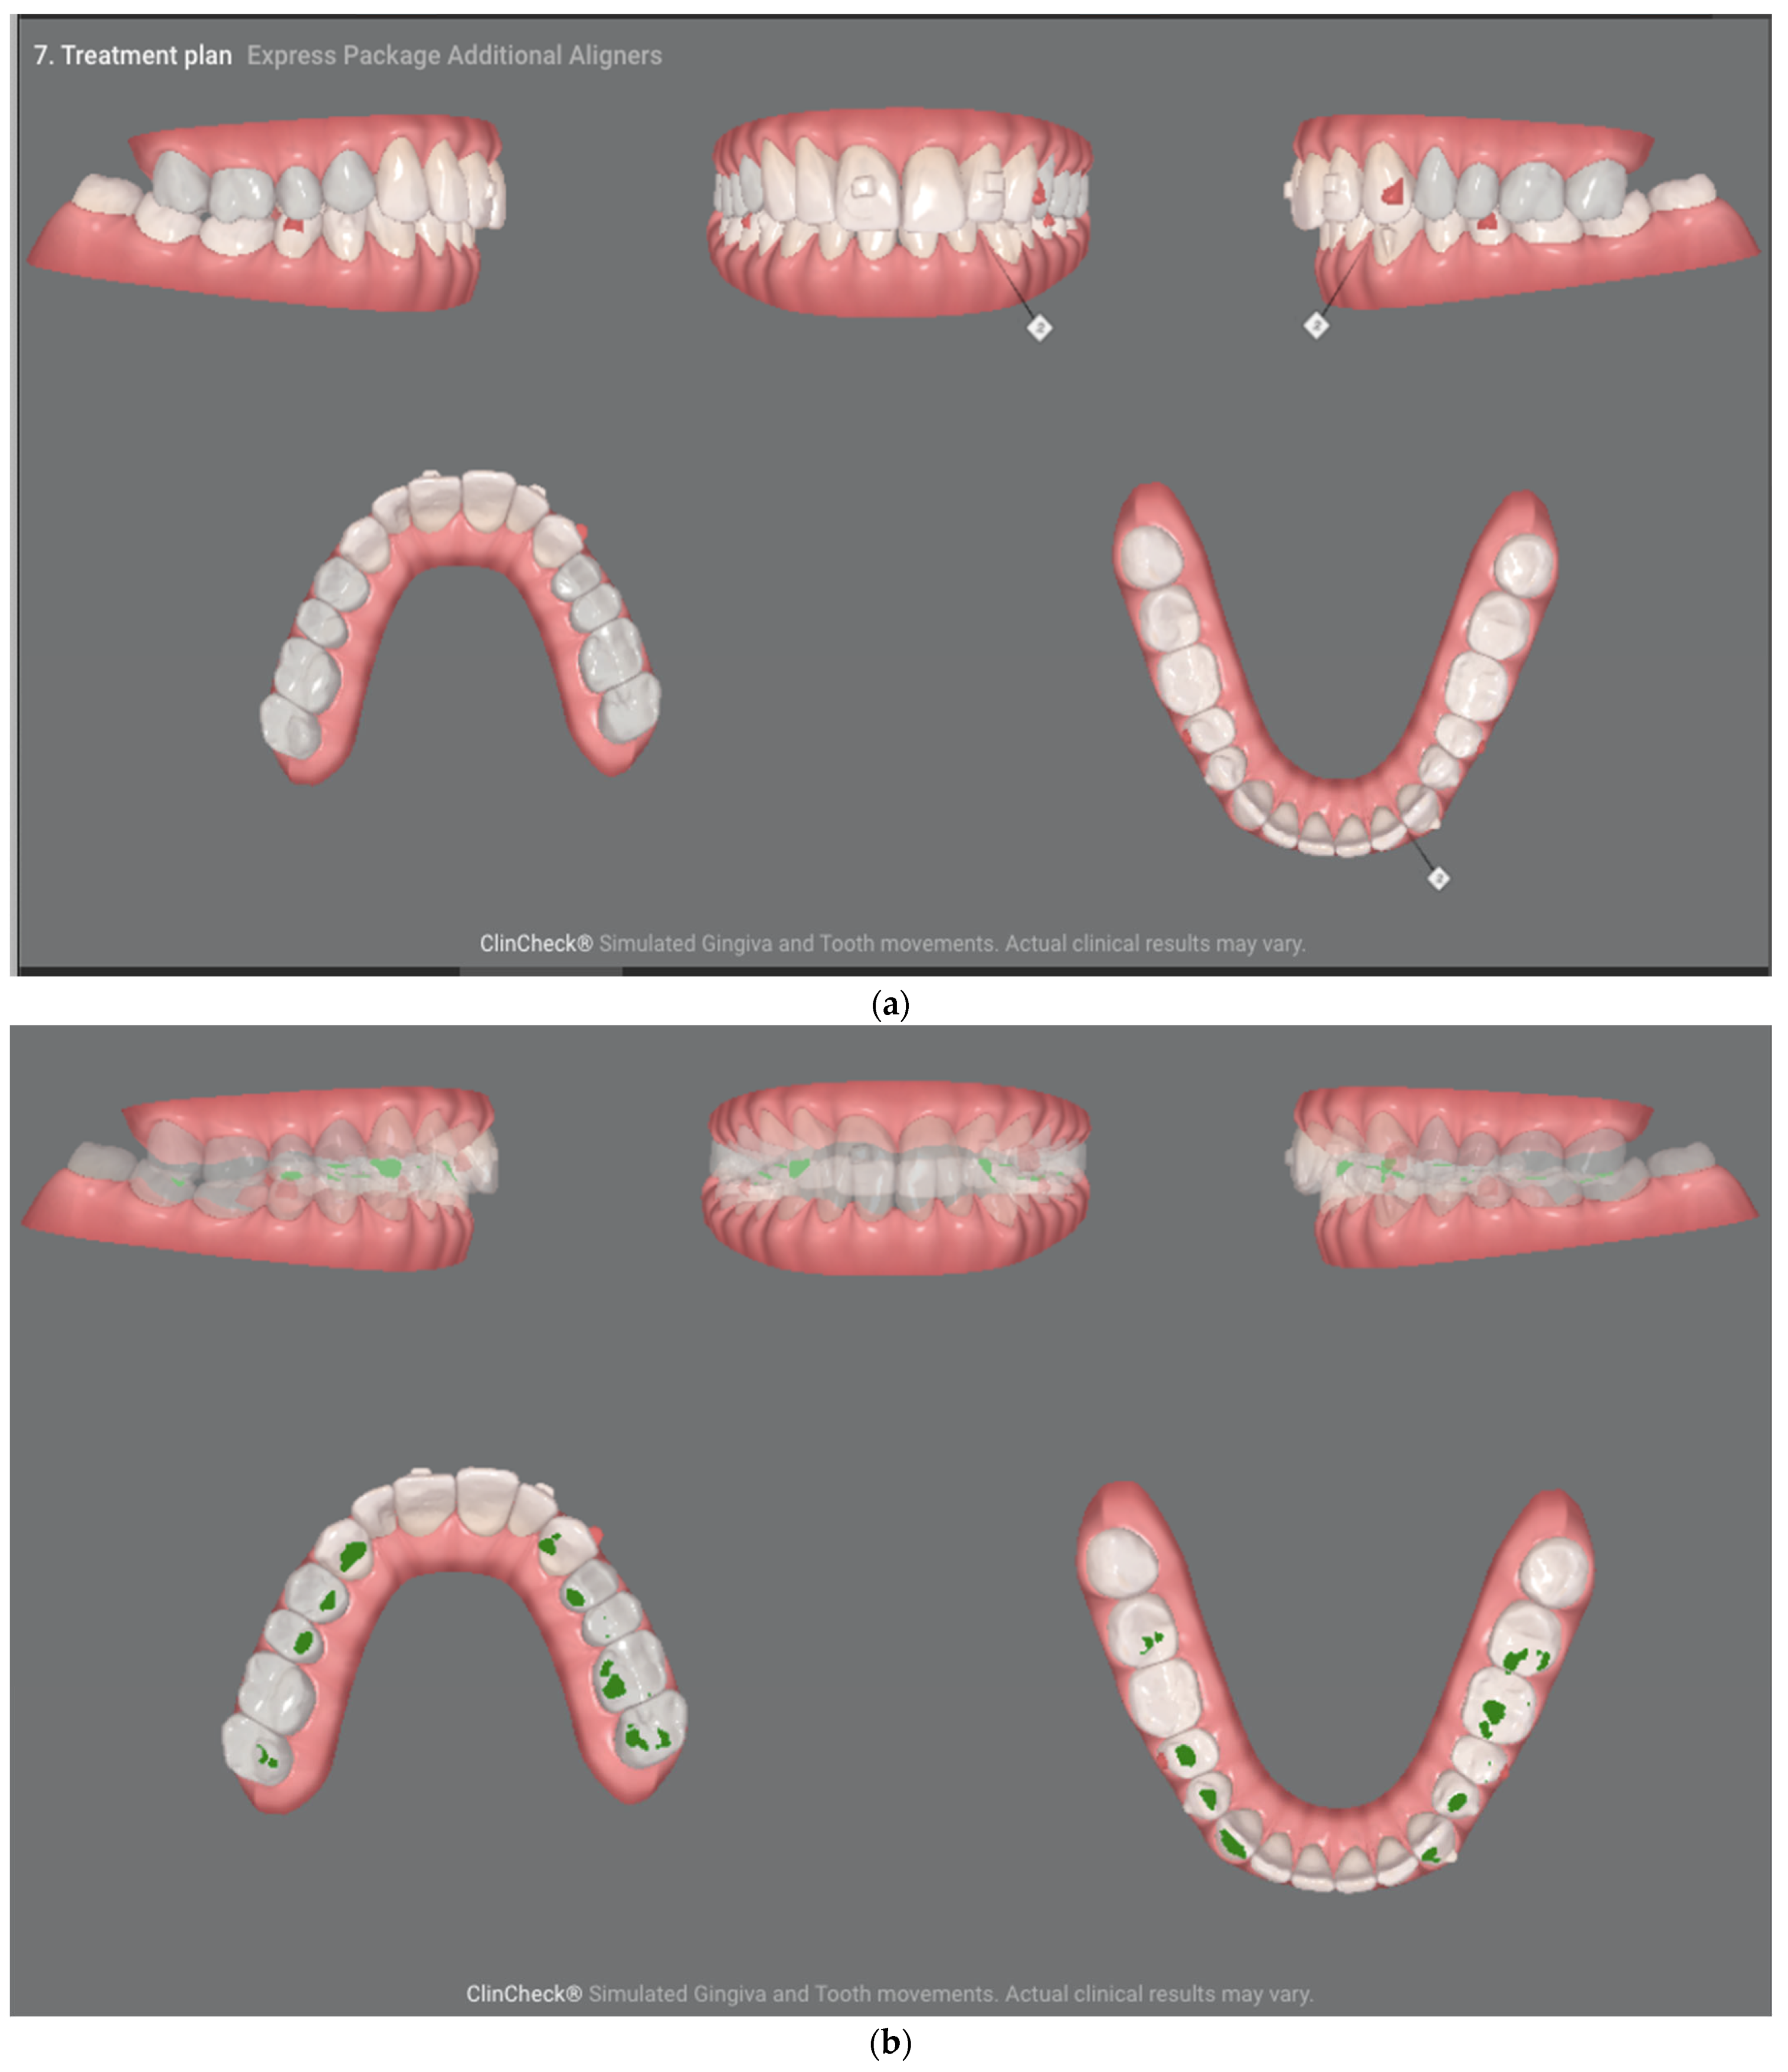

For this reason, the plan was changed, extending the orthodontic treatment to include the lower arch—a significant intrusion of the lower incisors and canines from 0.5 mm to 1.4 mm, distorotation up to 9.3 degrees and lingual inclination up to 5.5 degrees were planned. Translational axial movements and isolated root movements were also planned, including even 5-degree lingual torque movements (Figure 8a,b). The main focus was on the movements of the lower teeth due to the need to minimize the inevitable resorption of the root apex of tooth 21 (Figure 8c,d).

Figure 8.

ClinCheck of the second treatment plan. (a) presents the movements of the crowns in the upper arch, (b) presents the movements of the roots in the upper arch (c) presents the movements of the crowns in the lower arch (d) presents the movements of the roots in the lower arch. The numbers in the tables are expressed in milimeters (mm) and degrees (°). I—intrusion, L—lingual, D—distal, M—mesial. The underlined numbers are to most extensive movements of the tooth—of all the presented movements.

- Movements of tooth crowns in the lower arch. Visible leading moves tooth no. 4.3 lingual inclination, distorotation, lingual translation; 4.2 distorotation, lingual inclination, intrusion; 4.1 lingual inclination, lingual translation; 3.2 lingual inclination and intrusion; 3.3 lingual inclination, distorotation, distal angulation, intrusion.

- Figure 8. (a) Movements of tooth crowns in the upper arch. Visible leading moves, 1.3—distortion, 1.1—distortion and buccal inclination, 2.1 distortion. (b) Movements of tooth roots in the upper arch. Leading movements tooth no. 1.3 distorotation, 1.2 distorotation, 1.1 distorotation and lingual inclination, 2.1 buccal inclination (c).

- Figure 8. Movements of tooth crowns in the lower arch. Visible leading moves tooth no. 43 buccal inclination, 4.2 distorotation and buccal inclination, 3.2 distorotation, buccal inclination, z. 3.3 distorotation and buccal inclination.